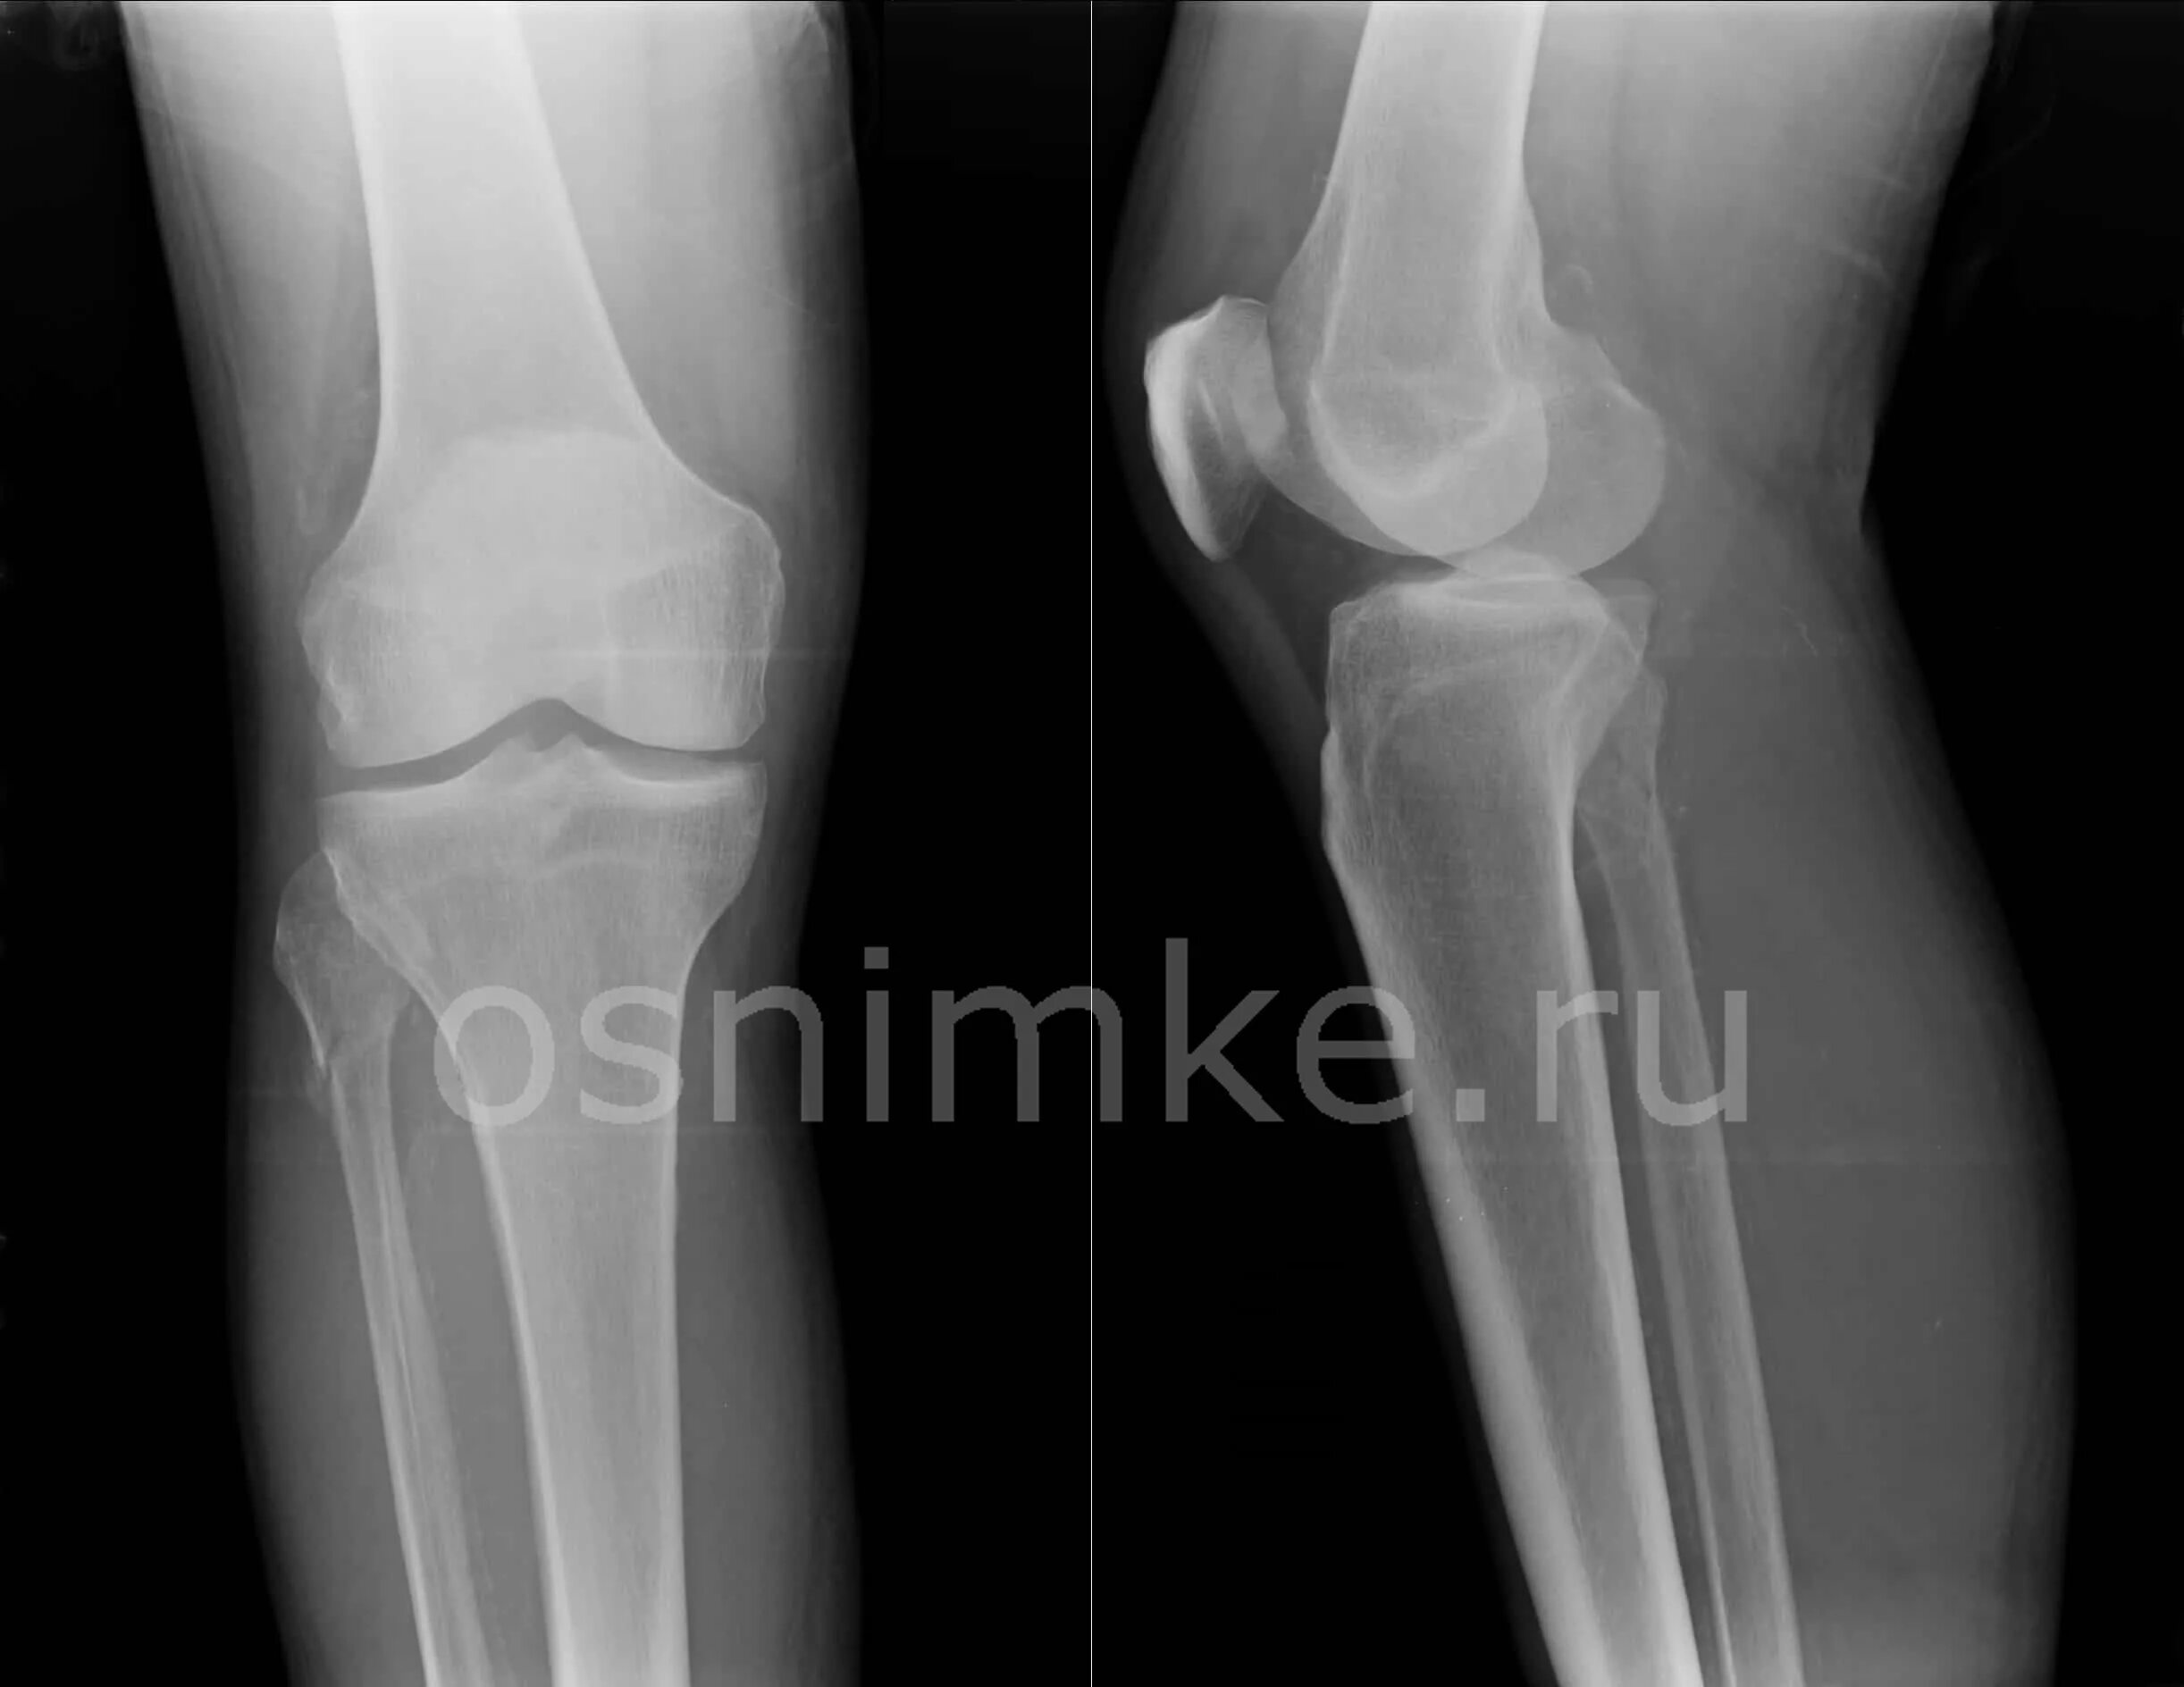

Рентгенография коленного сустава 2 проекции